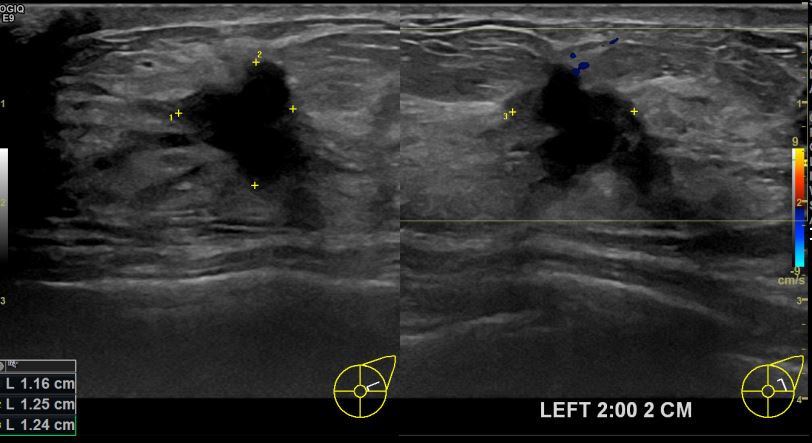

상기환자 외부검사상 이상소견으로 내원하신 60대여성으로 좌측유방의 의심스러혹

조직검사시행해 유방암 진단되었읍니다